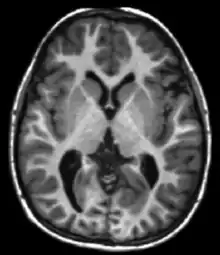

| Fluid-attenuated inversion recovery | FLAIR | Fluid suppression by setting an inversion time that nulls fluids | High signal in lacunar infarction, multiple sclerosis (MS) plaques, subarachnoid haemorrhage and meningitis (pictured).[15] | ![]() | |

Inversion recovery

Inversion recovery is an MRI sequence that provides high contrast between tissue and lesion. It can be used to provide high T1 weighted image, high T2 weighted image, and to suppress the signals from fat, blood, or cerebrospinal fluid (CSF).[40]